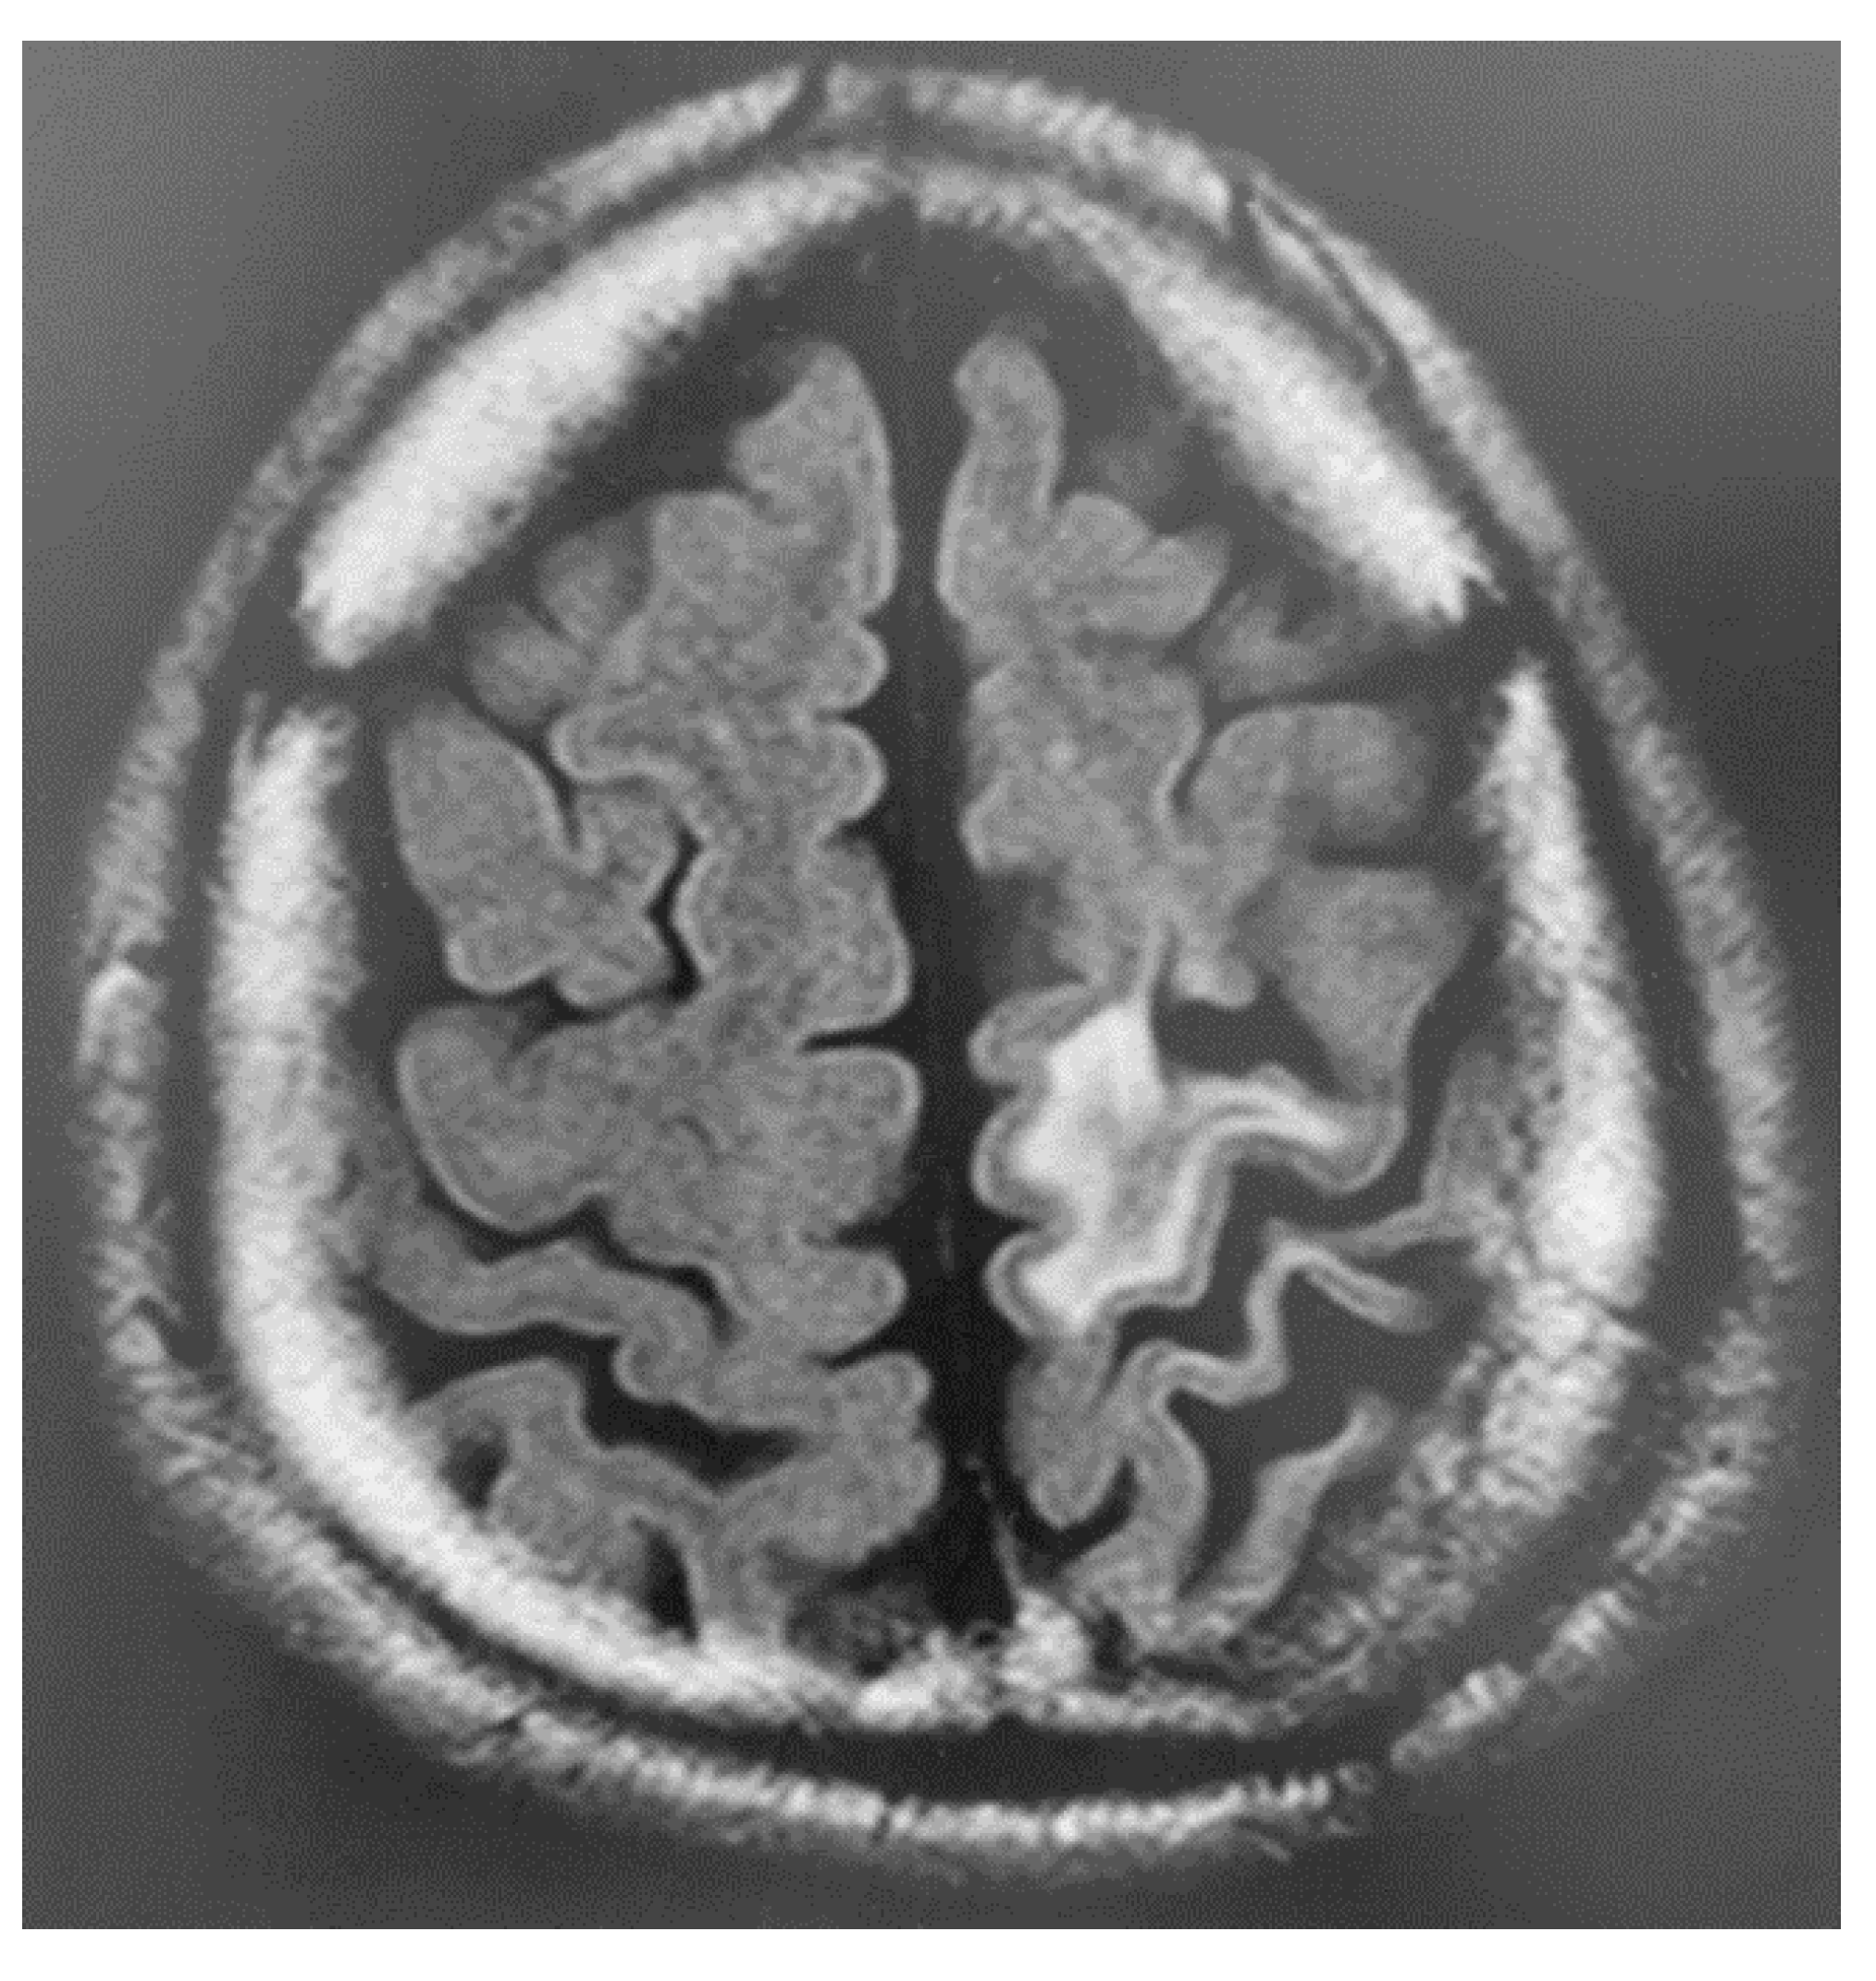

3. Instruments Used for Brain Imaging

Mechanism Underlying the Pathogenesis